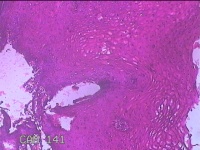

宫颈12点咬取物

性别

女

年龄

20岁

临床诊断

人乳头瘤病毒感染

一般病史

宫颈人乳头瘤病毒感染16型阳性。

标本名称

大体所见

灰白粉红色组织0.8x0.5x0.2cm一块。

慢性宫颈炎

慢性宫颈炎伴HPV感染